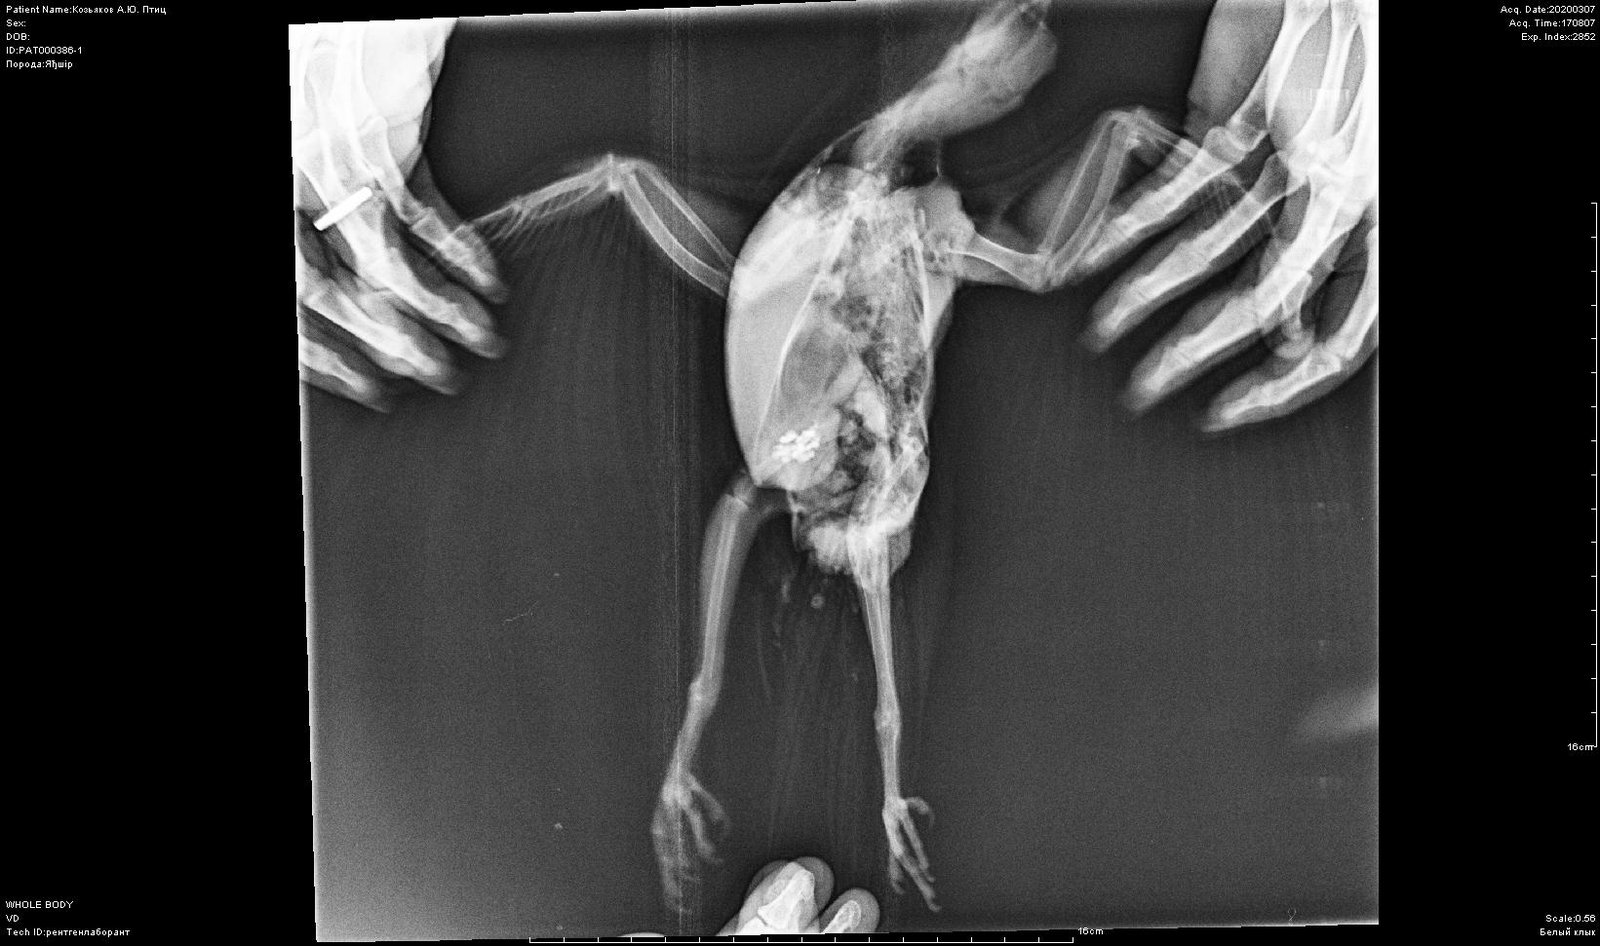

Elena1811 Опубликовано 7 марта, 2020 Автор #113 Опубликовано 7 марта, 2020 Мы старались как могли. Не получается его развернуть полностью из-за левого крыла. Не разворачивается доконца. Боялись сломать

Elena1811 Опубликовано 7 марта, 2020 Автор #115 Опубликовано 7 марта, 2020 5 минут назад, маленький принц сказал: позвал в тему Зосю Спасибо. Будем ждать. И надеюсь снимки читабельны

Elena1811 Опубликовано 7 марта, 2020 Автор #116 Опубликовано 7 марта, 2020 Нам их дополнительно скинули на флэшку

Zosia Опубликовано 7 марта, 2020 #124 Опубликовано 7 марта, 2020 Если есть файлы на флешке- то мне на почту киньте. Т.к. в переснятом виде снимки нечитабельны. zofia68@mail.ru

Elena1811 Опубликовано 11 марта, 2020 Автор #130 Опубликовано 11 марта, 2020 Получила ответ от Зофии. Нужны разъяснения. И некоторые препараты я не могу купить Вот что пишет Зофия: Ну, отличить голубя от голубки я по фото не смогу. Хотя ИМЪО мне видится голубка. И те новообразования в брюшной полости (которые могцт передавливать нервные окончания, идущие к лапкам)- характерны именно для голубок, у меня даже фото есть гранулем, которые у них «рождаются» вместо яиц. Так что ИМХО- итраконазол в дозе 15 мг/кг каждые 12 чсов, нисиатин в дозе 75 000 ед в сутки на 100 гр веса, преднизолон из арсчета 3 мг/кг в сутки. Первый курс- 21 день. Для прикрытия преднизолона- Деринат капли назальные, принимать орально 4 капли в сутки весь курс. Обязательно гепатовте- 0,2-0,3 мл в сутки. По крылу- ваш снимок не дает возможности оценить фатальность нарушений. Но скорее всего- там уже вряд ли что можно сделать (и по-любому это вопрос-не вопрос жизни). ......... У нас беда с преобретением лекарств, рецепты только лишь на аналгин не нужны..